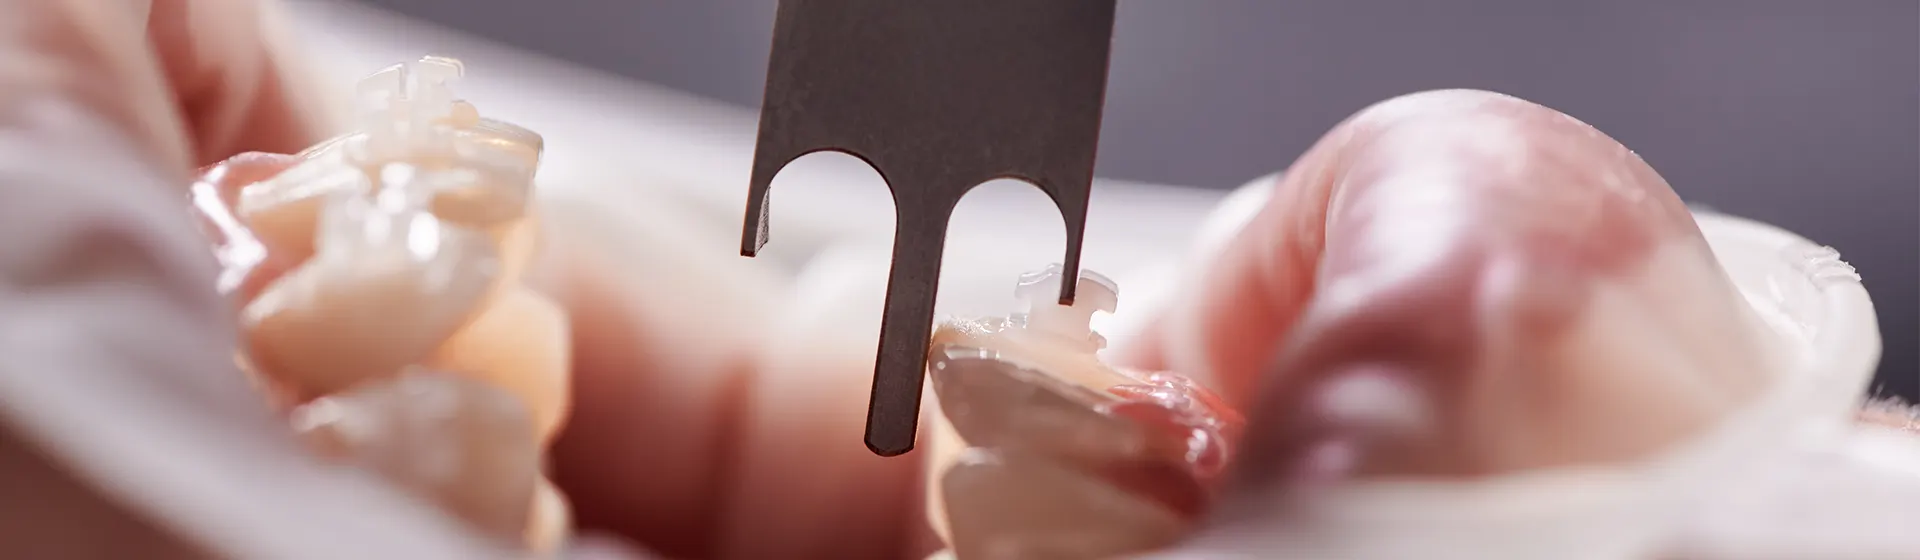

Introduction: Dr Doaa Mufleh is a pediatric dentistry specialist from jordan, She graduated from the university of Jordan in 2010 with a degree of Doctor of dental surgery (DDS), then she enrolled in the Jordanian royal medical services as a resident in pediatric dentistry , She obtained the Jordanian board of pediatric dentistry from the Jordanian medical council in 2016 , She has an experience of 14 years at the hospitals of the royal jordanian medical services in jordan, including Queen Rania speciality hospital ,King Hussein medical centre, Princess Haya hospital,her work included clinical part and training of new residents in pediatric dentistry including lectures and examinations, and one year experience in Dubai,she is also a member of the royal college of surgeons in ireland,(MFD, RCSI)member of the jordanian dental association, and jordanian pediatric dentistry association.

She is certified in nitrous oxide sedation from Dubai, and works with medically fit patients, patients with special health care needs on the dental chair and under general anesthesia. She is an active attendant of multiple international conferences and always following continuous dental learning and training courses and programs.

Dr Doaa’s passion is pediatric dentistry, and drawing a smile on little kids faces, she believes a good pediatric dentistry practice is the foundation for a life long good dental health, thats why she takes the responsibility of giving her patients the best first dental visit experience where she can build a safe dental home for them.